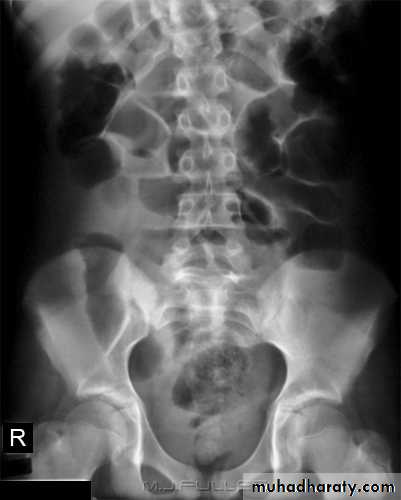

Abdominal calcifications

Assessment of the shape and pattern of abdominal calcification will usually limit the diagnosis to one or two choices. Calcification in the abdomen are likely to be :1. Pelvic vein phleboliths: very common, may be mistaken for urinary stones & fecoliths

2. Calcified mesenteric LN: caused by old TB. They are irregular, very dense and mobile

3. Vascular calcification: e.g. aortic aneurysm which best assessed on lateral film

4. Uterine fibroids: irregular shaped well-defined calcifications conforming to the spherical outline of fibroids

5. Soft tissue calcification in buttocks following injection of certain medicines

6. Ovarian masses may contain calcification. Dermoid cyst may contain teeth

7. Adrenal calcification after adrenal haemorrhage & TB, also in tumor & Addison disease

8. Liver calcification: occur in hepatoma, hydatid cyst, abscess and TB

9. Gall stones

10. Splenic calcifications in cysts, infarcts, old hematomas and TB

11. Pancreatic calcification: occur in chronic pancreatitis & diagnosed from it's position

12. Faecoliths seen in colonic diverticulae or in the appendix. The presence of appendicolith is a strong indicator of acute appendicitis, often with perforation.

13. Renal stones and other calcifications of the urinary tract